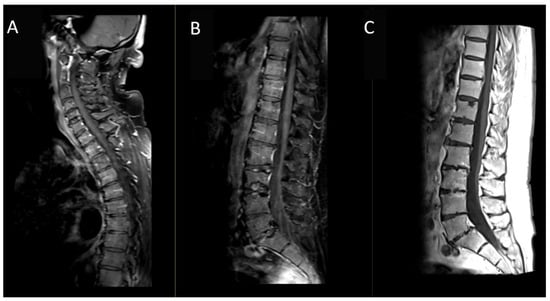

A 60-year-old Caucasian male presented with a secondary generalized focal motor seizure that caused post-ictal right hyposthenia, which resolved after 2 days. Neurological examination showed a slight leveling of the left lower limb during the Mingazzini maneuver, hyperelicitable osteotendinous reflexes in the four limbs with anisoreflexia left > right, pathological Babinski’s sign on the right, and hypopallesthesia of the lower limbs prevalent on the right with a cranio-caudal gradient. The patient had suffered from Waldenstrom macroglobulinemia 6 years before, but he recovered after treatment with Rituximab and Bendamustine. The patient did not have a history of epilepsy or any recent history of fever, vaccine, upper respiratory tract infection, abdominal symptoms, trauma, or travel. He suffered from psoriatic arthritis in treatment while taking Apremilast (300 mg × 2/day). At the time of presentation, the routine blood tests were unremarkable except for a slight increase in erythrocyte sedimentation rate (21 mm/h), lymphocytopenia (0.9 × 102/μL), and thrombocytopenia (127 × 103 μL). An unenhanced brain CT scan at the clinical onset revealed faint hyperdensity in some left parietal subarachnoid spaces (SHSs), which replaced the physiological hypodensity of the liquor (Figure 1). Patients underwent MRI scan after 5 days that revealed pathological signal and leptomeningeal enhancement on both left and right parietal SHSs without diffusion restriction (Figure 2). Further MRI examination performed one week later was negative for spinal cord and radicular/cauda equina alterations (Figure 3) but confirmed the stability of leptomeningeal findings. Leptomeningeal contrast enhancement was suspected for leptomeningitis, post-ictal hyperemia, and metastasis. After 20 days, the patient also underwent a total body CT scan to exclude any primary malignancies. Peripheral blood tumor marker (CEA, aFP, CA19-9, CA125, TPA, PSA, NSE, CYFRA), infective (HSV, HZV, JVC, EBV), and autoimmunity (anti-dsDNA, anti-RNP, anti-Sm) tests were negative. More than one month after the onset, cerebrospinal fluid (CSF) analysis documented the presence of monoclonal bands (light chain k, IgM) with elevated IgM index (0.45) calculated by [CSF IgM (mg/L)/serum IgM (g/L)]/[CSF albumin (mg/L)/serum albumin (g/L)] that is [1.89 (mg/L)/7.13 (g/L)]/[28.3 (mg/L)/48 (g/L)]. CSF flow cytometry revealed 2527 cells and 850 lymphocytes (33.64%). Among CSF lymphocytes, 87% of them were CD3+ CD5 +, while only 8% of them were CD19+ CD20+. The CSF tests did not reveal the presence of infectious meningitis (HSV1, HSV1, EBV, Adenovirus, Enterovirus, Parechovirus). The polymerase chain reaction test was negative for the L265P mutation in the MYD88 gene in both CSF and blood samples. CSF and MRI findings, along with the history of WM, were used to suggest the diagnosis of BNS within 2 months of the clinical onset (diagnostic timeline, Scheme 1). Therefore, brain tissue biopsy was not performed. A treatment with ibrutinib (140 mg three times daily) was initiated for the patient and is still receiving it. During a 1-year follow-up, there have been no new neurological signs or symptoms. The latest brain MRI showed a new subcortical left parietal lesion (18 mm) that was suspected to be caused by neoplastic cells infiltrating white matter vessels. Despite this, the spectroscopy map did not reveal any abnormal metabolic peaks in the lesion (Figure 4). The patient accepted the diagnosis and started and followed the therapy correctly. Despite his thrombocytopenia worsening, he tolerated the treatment well.

Figure 3. Post-contrast MRI sagittal T1-weighted images: (A,B) with fat suppression and (C) without fat-suppression. MRI study of the spinal cord and cauda equina did not reveal pathological contrast enhancement attributable to other Bing–Neel syndrome localizations.